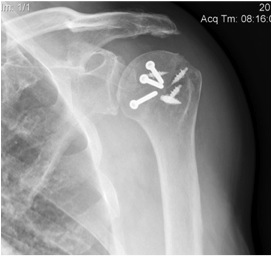

Results

- systematic review of modified McLauglin for locked posterior dislocation

- 9 studies and 97 shoulders

- reverse Hill Sachs 20 - 50%

- 100% union

- complication 1% (screw loosening)

- recurrent instability 2% (epileptic patients)